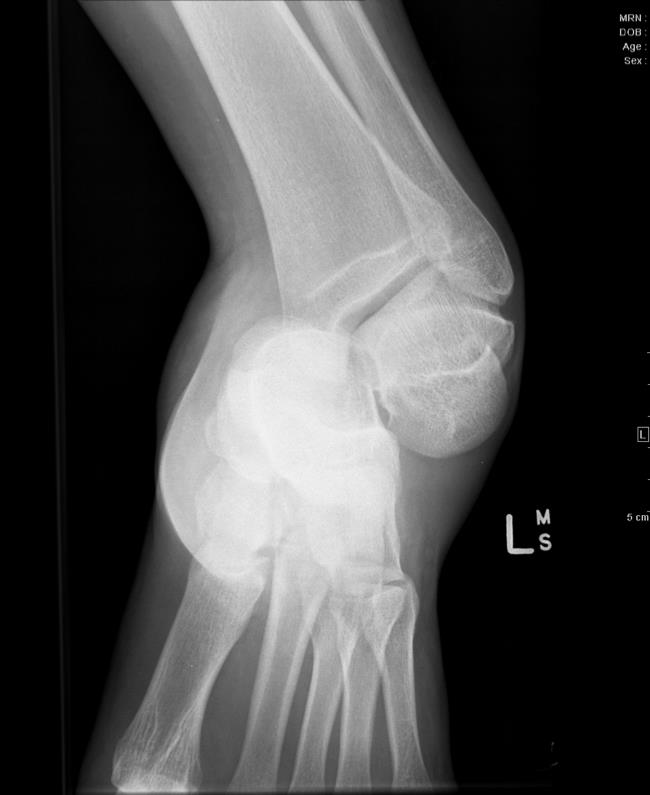

Figure A is the radiograph of a 32-year-old male who presents to the emergency department following a motor vehicle collision. You attempt a reduction of the closed injury but are unsuccessful. Which of the following structures is most likely to be preventing successful closed reduction?

This patient has a lateral subtalar joint dislocation. The posterior tibialis tendon is the most common structure preventing successful closed reduction.

Subtalar dislocations are hindfoot dislocations that result from high-energy trauma. The diagnosis is made clinically and confirmed with orthogonal radiographs of the foot. A lateral subtalar dislocation has been associated with fractures of the cuboid, anterior calcaneus, lateral process of talus, and the fibula. Treatment is a trial of closed reduction but may require open reduction given the several anatomic blocks to reduction. Blocks to a successful closed reduction of the lateral subtalar dislocation include medial-sided structures such as the posterior tibialis tendon (most common), flexor hallucis longus, and flexor digitorum longus.

Illustration A shows a posterior tibialis tendon preventing successful reduction of a lateral subtalar joint dislocation. Illustration B is the radiograph of the ankle demonstrating a medial subtalar dislocation.